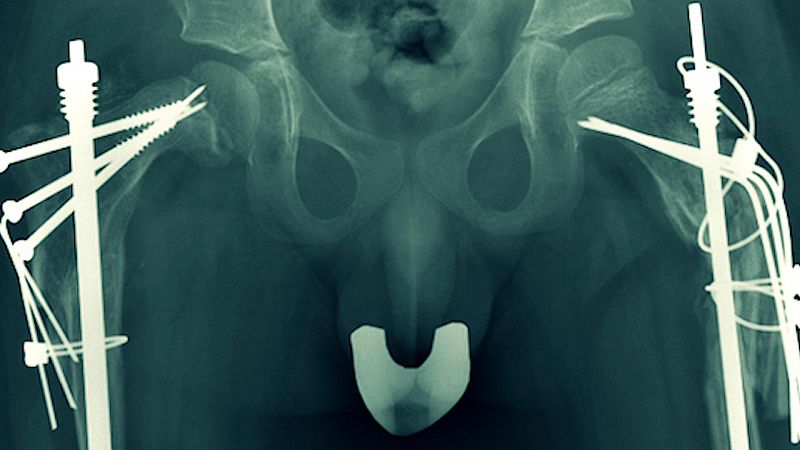

La batalla contra la destrucción del hueso responde a tratamientos farmacológicos y la cirugía, la solución urgente a las múltiples fracturas. Sin embargo, es la genética sobre la que recae la esperanza de los afectados, familiares y profesionales. De ella esperan, que algún día a no mucho tardar, las células óseas del paciente, sean capaces de generar hueso normal. Los especialistas auguran que en cinco o diez años pueden aparecer tratamientos satisfactorios en patologías congénitas.